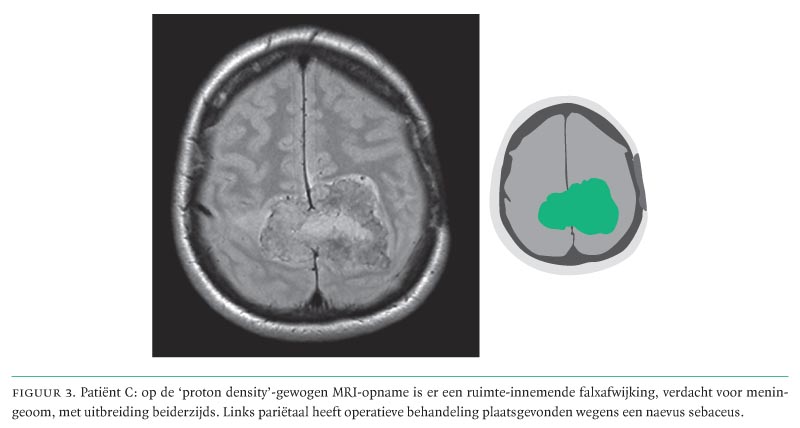

Bij lichamelijk onderzoek vonden wij een licht krachtsverlies van het rechter been, een hypesthesie van het mediale onderbeen en de voet rechts en een wat afgenomen coördinatie van de rechter hand. Patiënt maakte een adequate indruk. De MRI-scan van de hersenen toonde een bipariëtale falxafwijking, verdacht voor een meningeoom (figuur 3), hetgeen bij pathologisch onderzoek ook zo bleek.

Na haar operatie ging patiënte naar een revalidatiecentrum. Zij was blij niet dement te zijn zoals zij vreesde, maar betreurde wel dat alles zo gelopen was. Vervroegd stoppen met werken was niet wat haar oorspronkelijk voor ogen had gestaan. Toen zij 1 jaar na de operatie teruggezien werd op de polikliniek Neurologie, had zij als enig restverschijnsel een spastisch rechter been.